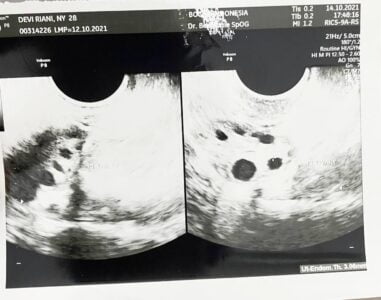

Pada bulan Oktober 2021, saya mencoba kembali memulai promil di RS Primaya Tangerang, mengikuti program promil di Bocah Indonesia. Kabar baik datang dari dokter, rahim dalam kondisi baik dan normal. Sperma suami juga dalam kondisi baik. Namun, ketika kami meminta obat, dokter menyarankan saya untuk menjalani HSG.

- Ultrasonography (USG) Transvaginal

- USG Transvaginal: Jika haid teratur, pemeriksaan dilakukan pada hari ke-2 hingga ke-5 menstruasi. Jika tidak teratur, bisa datang kapan saja tanpa perlu menunggu waktu haid.